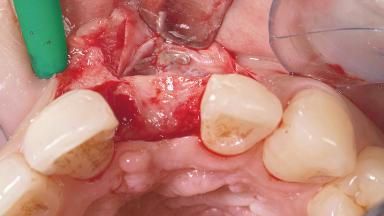

Late Placement of an Implant in a Maxillary Left Central Incisor Site

A 30-year-old female patient had lost tooth 21 and was referred to our clinic for consultation and treatment. Due to advanced apical infection, tooth 21 had been extracted two months earlier at another clinic and an acrylic-resin tooth had been bonded to the adjacent teeth. The patient desired implant treatment to avoid any damage to the adjacent natural teeth. While the patient had no history of any systemic disorder, she was a heavy smoker and exhibited medium to advanced periodontitis in the entire jaw. After the initial treatment to achieve a pocket probing depth of less than 4 mm and no bleeding on probing, a decrease in the height of the papillae mesial and distal to the extraction site and overall gingival recession were observed.

Bone Augmentation Horizontal|Staged

Augmentation Materials Autogenous chips|Membrane